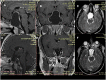

Objective: Rathke's cleft cysts (RCCs) are quite uncommon sellar lesions that can extend or even arise in the suprasellar area. The purpose of this study is to evaluate the effectiveness of both standard and extended endoscopic endonasal approaches in the management of different located RCCs.

Results: A standard transsphenoidal approach was used in 19 cases, while the extended variation of the approach in 10 cases (5 purely suprasellar and 5 intra-suprasellar RCC). Cysts contents was fully drained in all the 29 cases, whilst a gross total removal, that accounts on the complete cyst wall removal, was achieved in an overall 55,1% of patients (16/29), specifically 36,8% (7/19) that received standard approach and 90% (9/10) of those that underwent to extended approach. We reported a 56.2% of recovery from headache, 38.5% of complete recovery and 53.8% of improvement from visual field defect and an overall 46.7% of improvement of the endocrine functions. Postoperative permanent DI rate was 10.3%, overall post-operative CSF leak rate 6.9%; recurrence/regrowth occurred in 4 patients (4/29, 13.8%), but only one required a second surgery.

Conclusion: The endoscopic transsphenoidal approach for the removal of a symptomatic RCC offers several advantages in terms of visualization of the surgical field during both the exposure and removal of the lesion. The "extended" variation of the endoscopic approach provides a direct access to the supradiaphragmatic space, allowing adequate view and room for the safe removal of selected supradiaphragmatic RCCs, regardless of the sellar size (even a not enlarged sella), and provides a higher likelihood of preserving normal pituitary tissue and functions.